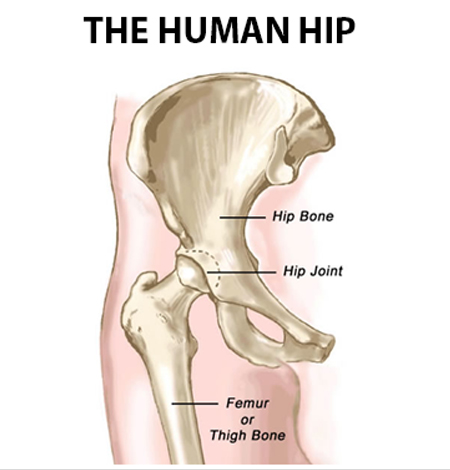

Primary Hip Replacement

Primary Hip replacement surgery involves replacing the damaged hip joint (ball and socket) with a body friendly implant known as prosthesis. Hip joints helps support and retain the balance of the body. Their primary function is to support the weight of the body in both static (e.g. standing) and dynamic (e.g. walking or running) postures.

Hip pain can be caused by sudden and serious injury or a degenerative condition like osteoarthritis. Other indications include rheumatoid arthritis, avascular necrosis, traumatic arthritis, certain hip fractures, benign and malignant bone tumors, arthritis associated with Paget???s disease,ankylosing spondylitis and juvenile rheumatoid arthritis.